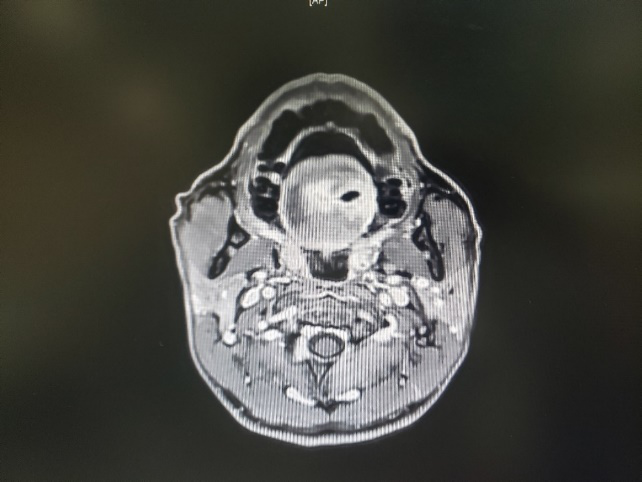

图一:患者的MRI

图二:患者的MRI

图三:患者的MRI